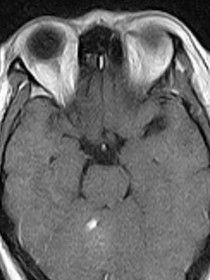

脫髓鞘疾病是一大類病因不相同,臨床表現各異,但有類同特徵的獲得性疾患,其特徵的病理變化是神經纖維的髓鞘脫失而神經細胞相對保持完整。髓鞘的作用是保護神經元並使神經衝動在神經元上得到很快的傳遞,所以,髓鞘的脫失會使神經衝動的傳送受到影響。急性脫髓鞘性疾病的神經髓鞘可以再生,且速度較迅速,程度較完全,雖然再生的髓鞘較薄,但一般對功能恢復的影響不大。慢性脫髓鞘性神經病,由於反覆脫髓鞘與髓鞘的再生許旺細胞明顯增殖,神經可變粗,並有軸突喪失,因此功能恢復不完全。

⑤創傷性。 olekmj將脫髓鞘疾病按照以下分類: 自身免疫性 急性播散性腦脊髓炎 急性出血性白質腦炎 多發性硬化 感染性 進行性多灶性白質腦病 中毒性/代謝性 一氧化碳中毒 維生素b12缺乏 汞中毒(minamata病) 酒精/菸草中毒性弱視 腦橋中央髓鞘溶解症 marchiafava-bignami綜合徵 缺氧 放射性 血管性 binswanger病 髓鞘代謝的遺傳性疾病 腎上腺白質營養不良 異染性白質營養不良 krabbe病 alexander病 canavan-van bogaert-bertrand病 pelizaeus-merzbacher病 苯丙酮尿症 臨床上最常見的是多發性硬化。這裡主要說說多發性硬化病的主要症狀、體徵等。多發性硬化是因為自身免疫障礙而導致的中樞神經系統的脫髓鞘性疾病。